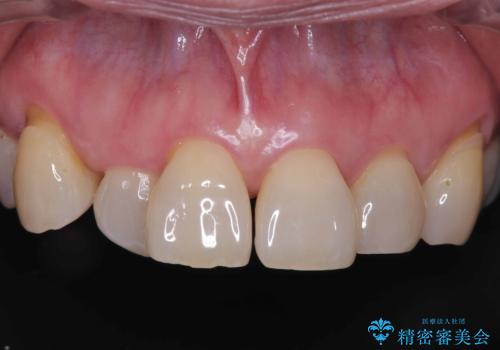

そのため今回は、右上2番を抜歯し、右上1番および左上1番をオールセラミッククラウンで審美的に修復しました。

治療期間も短く、抜歯からわずか3か月でオールセラミッククラウンを装着することができます。

また、オペ当日には仮歯まで装着するため、見た目を気にせず普段通りの生活を送ることができます。